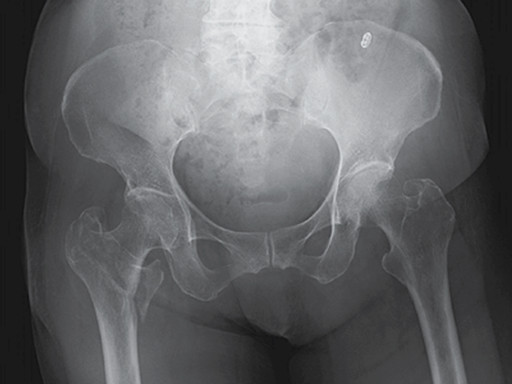

A 78-year-old Japanese patient fell while at her home and sustained an AO 31-A2.1 injury (see Fig 5).